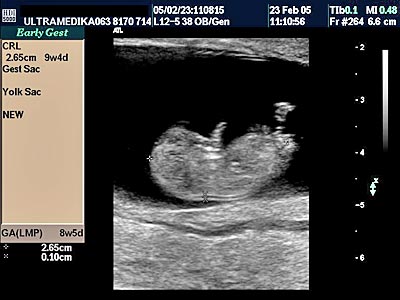

2. Da li je trudnoća vitalna ili ne?

Veoma često u prvim nedeljama trudnoće dolazi do oskudnog krvarenja koje kod trudne žene izaziva strah. Savremena UZ dijagnostika mora otkriti razlog ovog krvarenja. Najčešći razlog je manja subhorionska hemoragija, koja nastaje u toku formiranja posteljice i ne zahteva primenu hormonske terapije.

Jedna trudnoća se ne može smatrati vitalnom ako se ne registruje srčana radnja ploda. Čak šta više u zavisnosti od veličine ploda srčana radnja je različite učestalosti. Obaveza je doktora da M-modom tačno izmeri frekvencu srčane radnje. Usporen srčani rad u odnosu na starost trudnoće obično predstavlja loš prognostički znak za vitalnost trudnoće!